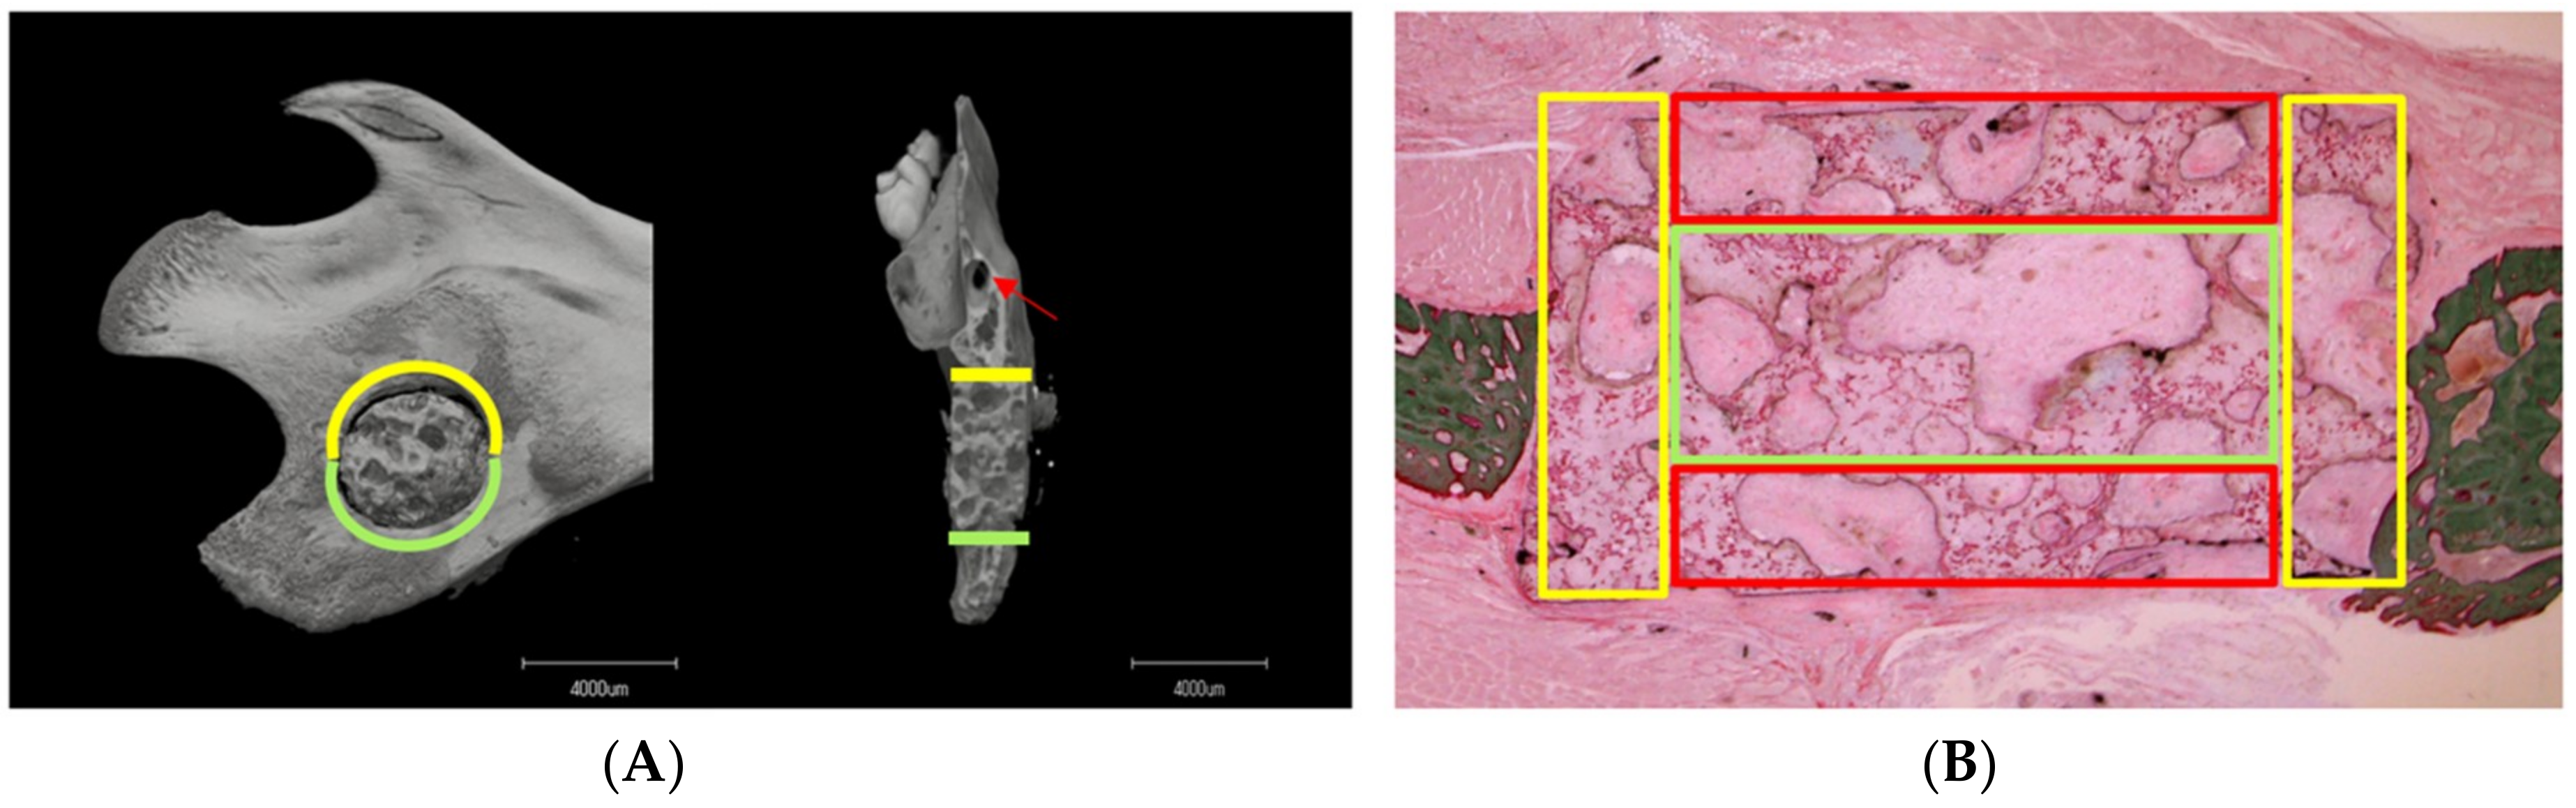

3.1. Micro-CT Analysis

3.1.2. Material–Host Bone Combinations and the Quantity of Newly Formed Osteoid Tissue

3.1.3. Difference in Osteogenesis between the Superior and Inferior Sides of the Critical Mandibular Defect

3.2. VG Staining Results

3.2.1. Description of VG Staining

3.2.2. Number of Nucleated Cells in Different Pore Areas